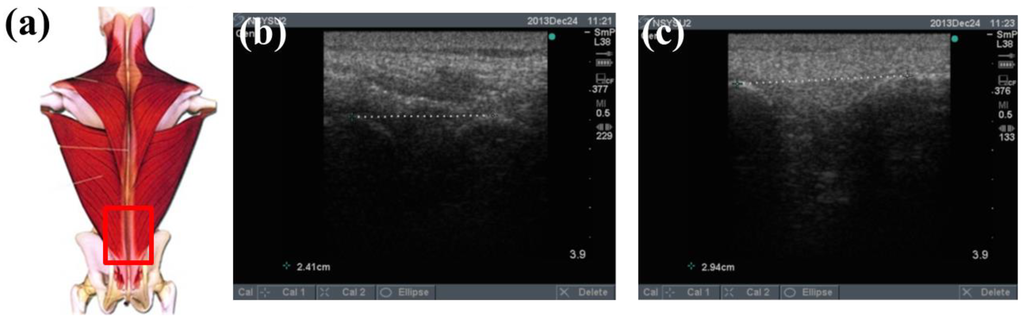

To determine the feasibility of the training system proposed in this study, we used ultrasound imaging to observe the muscles' length changes during contraction and determined whether these changes were correlated with skin stretches. Ultrasound image measurement is used for exploring the human body, such as observing tissue structure, blood or tissue movement, and the mechanical characteristics of tissues. Tissue structure is mainly observed using grayscale images. The primary principle in ultrasound imaging is the reflection of ultrasound waves when the waves encounter different density interfaces in the human body. The piezoelectric crystals in the sensor head receives the signals and converts the signals into images according to the direction, distance, and strength of the waves. Ultrasound imaging is often used to examine tumours, tissues, or organs inside the body. Moreover, ultrasound images are also usually used to exam the muscle and soft tissue in rehabilitation and orthopaedic departments [12–16]. The SonoSite Titan ultrasound system (FUJIFILM SonoSite, Inc, Bothell, WA, USA) was used to measure the muscle length changes during exercise. The trapezius, mid erector spinae, and lower erector spinae were measured. The ultrasound image of the muscles at different trunk angles during Roman chair back hyperextension training is shown in Figures 10, 11 and 12, the (b) component showed the image in the preparatory actions and (c) component showed the image in the flexion 45 degrees. The muscle length in the specific positions is shown in Table 6. The lower erector spinae shown in Table 6 had a muscle shortening length of 0.53 cm (the largest length change). The test position correspond to skin stretch of 20%–35%, as shown in Figure 3b, was the largest change among the three positions. The results showed that during Roman chair back hyperextension training, changes in back skeletal muscle extension length exhibited a positive correlation changes in skin stretch. Therefore, the feasibility of a proof of concept sensor has been demonstrated.

| Trapezius Back Skeletal Muscle Extension Length (cm) | Mid Erector Spinae Extension Length (cm) | Lower Erector Spinae Extension Length (cm) | |

|---|---|---|---|

| Preparatory action | 2.47 | 2.94 | 2.94 |

| Anteflexion | 2.61 | 3.17 | 2.41 |

| Corresponding skin stretch | 0%–3% | 3%–12% | 20%–35% |